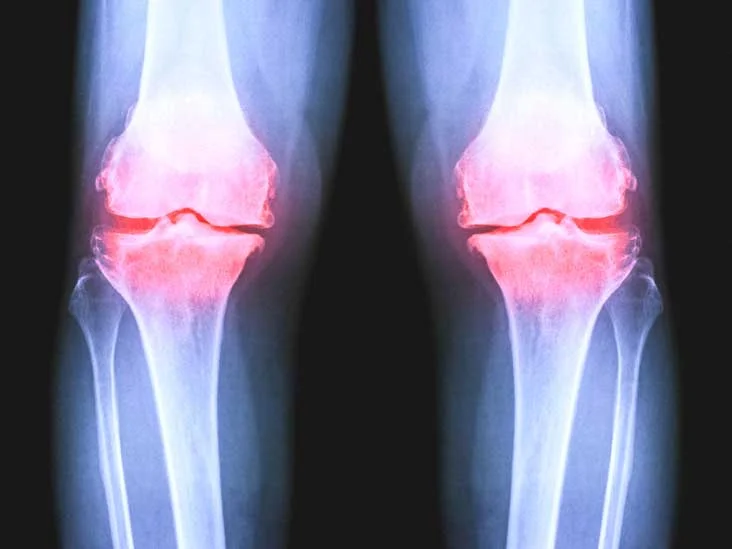

Gonartrosi femoro tibiale

Il ginocchio è una struttura complessa e fondamentale del nostro corpo. Collega la coscia e la gamba, permettendoci di muoverci liberamente. La cartilagine articolare svolge un ruolo primario in quest’area, proteggendo e ammortizzando le ossa degli arti inferiori durante i movimenti. La struttura anatomica del ginocchio Il ginocchio si compone di due articolazioni principali: la prima … Continued